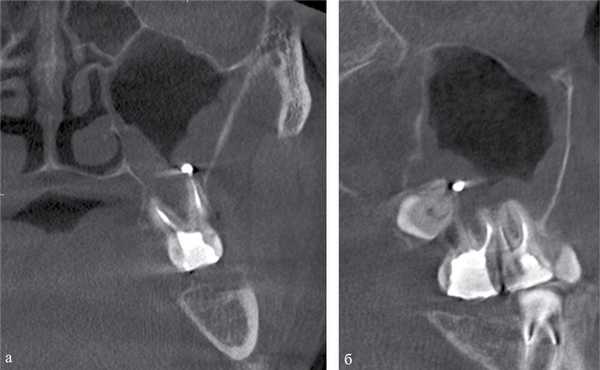

Рис. 2. МСКТ. Коронарная (а) и сагиттальная (б) реконструкции правого верхнечелюстного синуса пациента К., 29 лет. Диагноз: правосторонний одонтогенный хронический верхнечелюстной синусит. Корни зубов 1.6, 1.7 и 1.8 погружены в полость верхнечелюстного синуса. Состояние после эндодонтического лечения зубов 1.6 и 1.7, с выведением пломбировочного материала за верхушку небного корня 1.7. В области корней зубов 1.6 и 1.7 отмечается разрежение костной ткани с нечеткими неровными контурами (рентгенологические признаки гранулирующего периодонтита). В нижнем отделе синуса определяется пристеночное мягкотканное образование с полицикличным контуром, костные стенки синуса в данной области не прослеживаются.

Рис. 3. КЛКТ. Сагиттальная реконструкция, правый верхнечелюстной синус. Пациент У., 48 лет. Диагноз: правосторонний одонтогенный хронический верхнечелюстной синусит. Зубы 1.6 и 1.7 после эндодонтического лечения, отмечается выведение пломбировочного материала за верхушки корней зуба 1.6 (материал располагается в костной ткани альвеолярного отростка и в подслизистом слое синуса). Определяется разрежение костной ткани в области корней 1.6 и 1.7, костная стенка синуса в данной области не прослеживается (стрелка). В нижнем отделе синуса определяется утолщение слизистой оболочки до 10 мм, в верхнемедиальном отделе синуса визуализируется инородное тело неправильной формы металлической плотности (соответствует фрагментам пломбировочного материала).